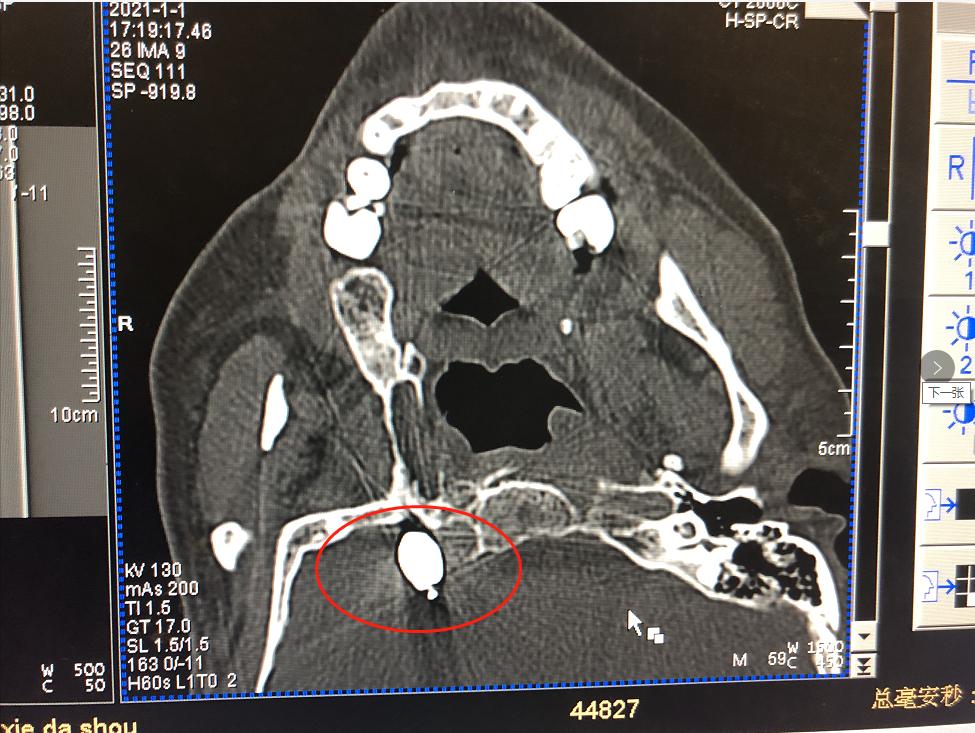

疼痛来得快,也去得快。缓过劲来的刘大伯到附近医院去看医生,被诊断为三叉神经痛,医生为他开了药。早期还有些效果,疼痛很快就能缓解,渐渐地,疼痛变得如影随形,不经意间便又冒出来,说话、吃饭、洗脸、刷牙等生活中常见的行为均可诱发疼痛。 无奈之下,饱受疼痛折磨的刘大伯去了芜湖的多家医院求治,疼痛科、神经内科就诊,基本上都是进行药物治疗,疼痛时好时坏。由于长期大剂量服药,药物治疗的副作用越发显现,这让他苦不堪言,严重影响了他的生活质量。 02不到20分钟的微创手术,彻底解除疼痛烦恼 最近,刘大伯的疼痛发作更频繁了,一吃东西就痛,痛起来更是痛不欲生,根本吃不了东西,被折磨得有气无力。 刘大伯慕名来到我院疼痛科就诊。疼痛科的秦学智主任了解了刘大伯的病情后,秦主任根据他的病史和身体情况,与团队进行了缜密分析和探讨,决定为其实施球囊压迫术解除三叉神经痛。 经秦主任详细解释后,刘大伯和家人欣然同意接受手术。 微球囊压迫术 微球囊压迫术被称为“针尖内的手术”,整个创口仅一个针眼大小,操作时间短,此次手术在局部麻醉下进行,患者全程为清醒状态,此手术具有创伤小、风险小、见效快、恢复快、复发率低的优点。 术中定位进针球囊进入

术中定位

进针

球囊进入